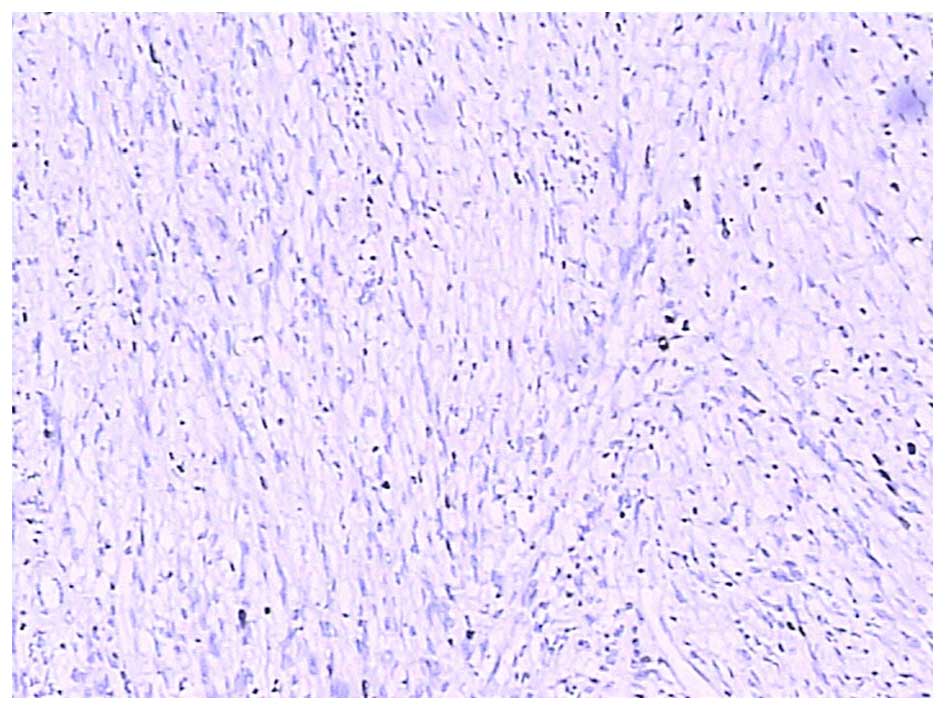

Figure 5.

c-Kit proto-oncogene (CD117) strong and diffuse cytoplasmic staining; magnification, ×100.